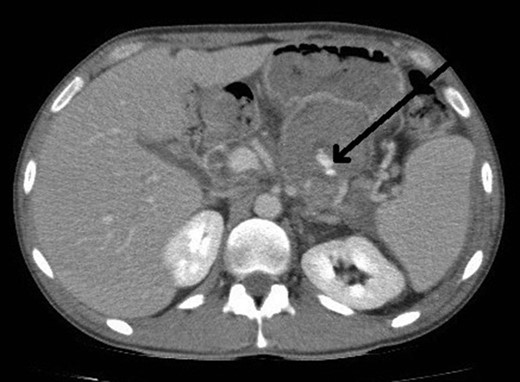

However, 4 days after the ultrasound guided injection, the patient collapsed on the ward with haematemesis and hypovolaemic shock. He was resuscitated initially with intravenous fluids and transfusion of blood products and remained alert with no abdominal signs. An emergency gastroscopy showed a 1.5 cm gastric ulcer on the posterior gastric wall with a large clot in the upper stomach but no active bleeding. A repeat CT abdomen demonstrated persistent flow in the pseudoaneurysm (Fig. 4).

CT abdomen image post thrombin injection shows flow in the pseudoaneurysm (arrow).